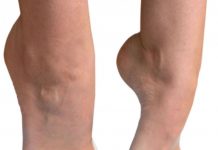

Ортопедические корректоры стопы и пальцев ног

Когда человек хочет купить себе красивую обувь, это становиться явной проблемой, потому что у него проблемы с ногами, а в красивой обуви любой шаг...